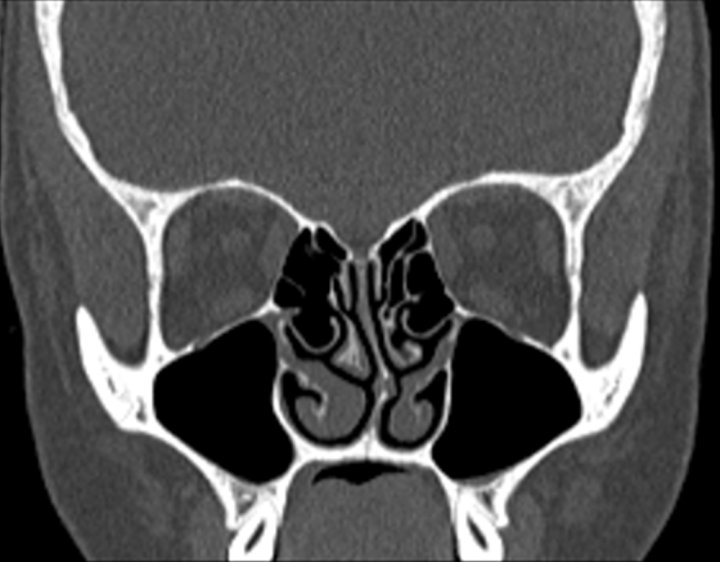

Click any image for labels.